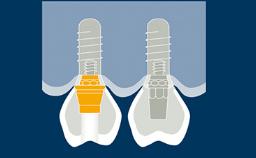

Prosthodontic Planning and Procedures

Abutment Selection for Fixed Dental Prostheses

Learning Module